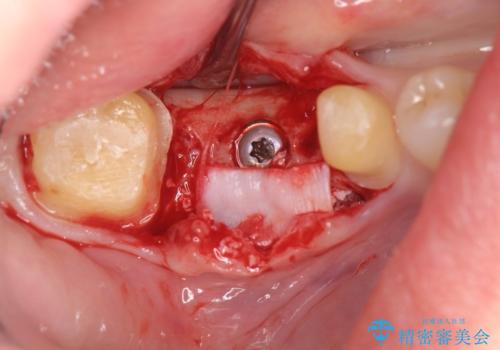

- 虫歯で歯を失い、インプラント治療を希望され来院されました。

吸収した骨を造骨にて補い、インプラントによる機能回復を計画します。

歯を失ってからの時間が経過し骨が吸収してしまっていても、造骨を行うことで予知性の高いインプラント治療を行うことができます。